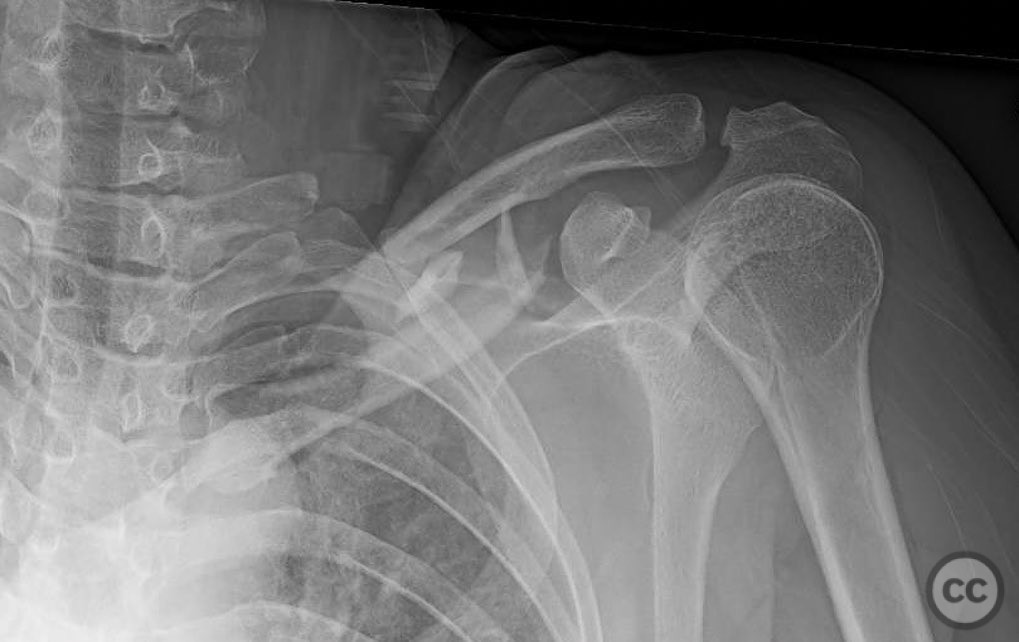

Clinical and radiological findings:  A 35-year-old male presented with an open diaphyseal clavicle fracture following a high-energy motorcycle accident. The fracture was classified as a simple diaphyseal pattern with two butterfly fragments, according to the AO/OTA classification system, specifically 15-B2. The patient exhibited significant soft tissue injury but no neurovascular compromise. Initial radiographs confirmed the fracture pattern, and the wound was thoroughly irrigated and debrided in the emergency department.